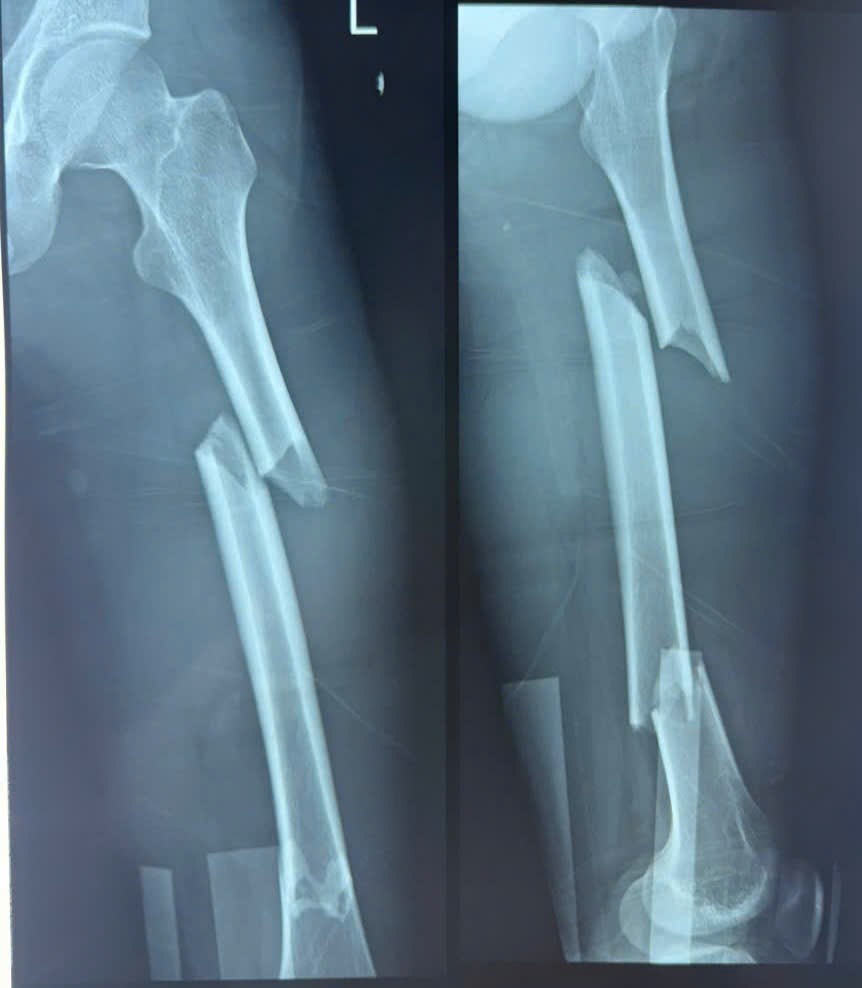

Ngay khi nhập viện, ekip Khoa Ngoại Thần kinh – Chấn thương chỉnh hình lập tức tiến hành hội chẩn khẩn. Kết quả cho thấy bệnh nhân bị gãy hai tầng xương đùi trái – một dạng chấn thương phức tạp, có nguy cơ ảnh hưởng nghiêm trọng đến khả năng vận động.

| Vị trí xương đùi trái bị gãy phức tạp của nạn nhân trong vụ tai nạn giao thông. |